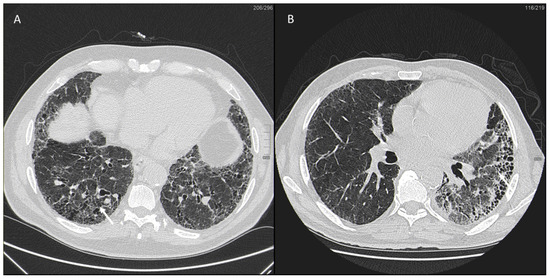

IPF is a chronic, irreversible, disabling disease with a fatal outcome characterized by a progressive decline in lung function. It is associated with a radiological pattern of usual interstitial pneumonia (UIP). In the literature, women have shown less fibrotic alterations than their male counterparts at HRTC (Figure 4).

Figure 4.

(A) Diffuse ground glass opacities with reticular thickening of the subpleural interstitium (white arrow), together with traction bronchiectasis in a case of pulmonary fibrosis with UIP pattern and smoking-related interstitial lung disease (ILD) in a female smoker. (B) A typical UIP pattern in a male smoker with idiopathic pulmonary fibrosis, together with diffuse ground glass opacities (white arrow) during an acute exacerbation.